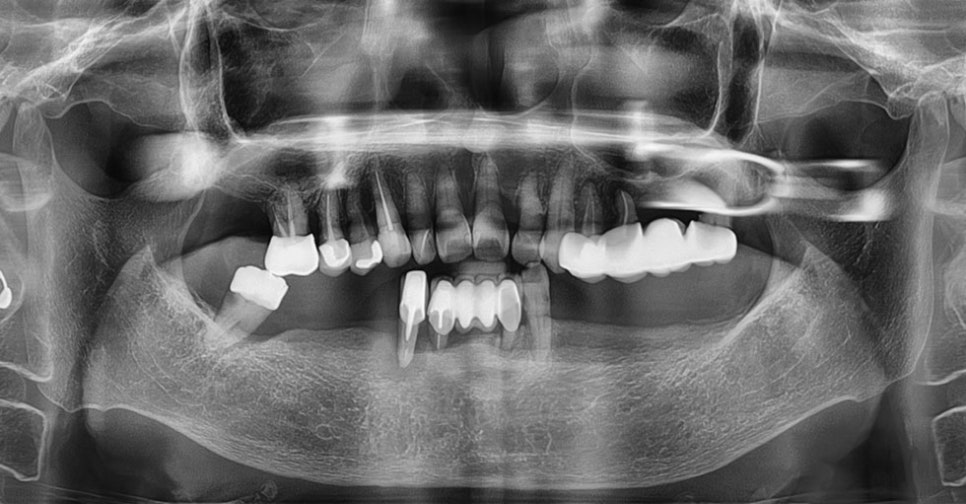

위의 사진은 3D로 CT를 컴퓨터 분석하는

모습이며 이렇듯 강남임플란트잘하는치과

본 치과에서는 임플란트 치료의 전 과정을

디지털로 진행하고 수술 전 3D 모의 수술을

통해 알맞은 수술 경로를 찾아

골조직과 신경 위치 등을 명확히 파악하여

신속하고 안정적인 수술 경로로 진행합니다.

따라서 개인의 구강 구조와 잇몸뼈에

알맞은 식립 위치와 각도, 깊이까지

파악하여 튼튼하게 치료할 수 있습니다.